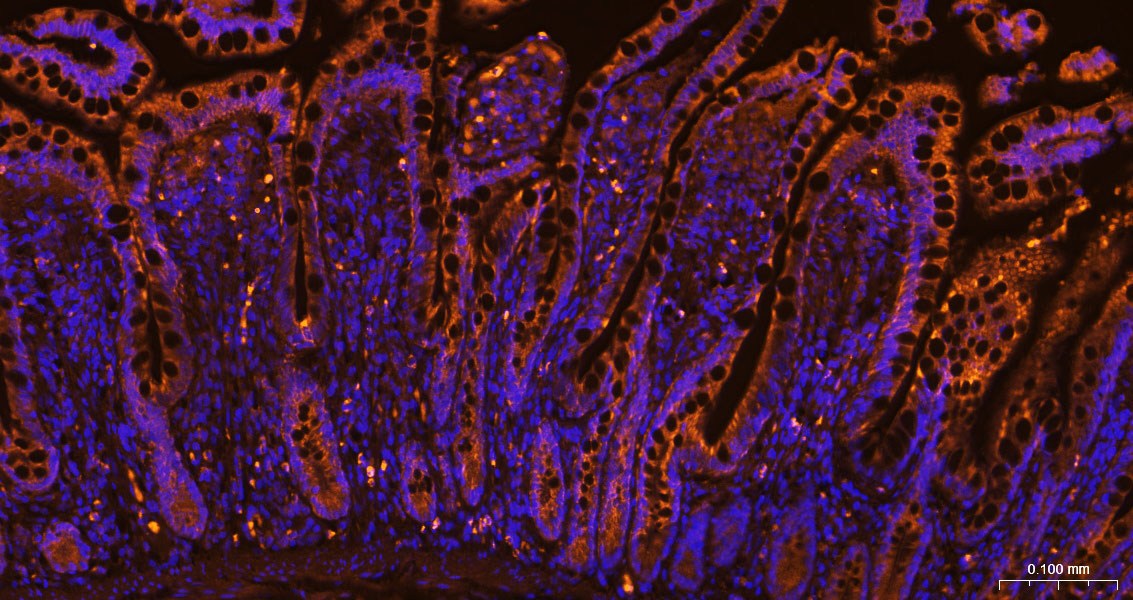

COX4I1 Monoclonal Antibody, Cy3 Conjugated

Product Name COX4I1 Monoclonal Antibody, Cy3 Conjugated

Conjugation Cy3

Synonyms Cytochrome c oxidase subunit 4 isoform 1, mitochondrial; COX4I1

Background This protein is one of the nuclear-coded polypeptide chains of cytochrome c oxidase, the terminal oxidase in mitochondrial electron transport.